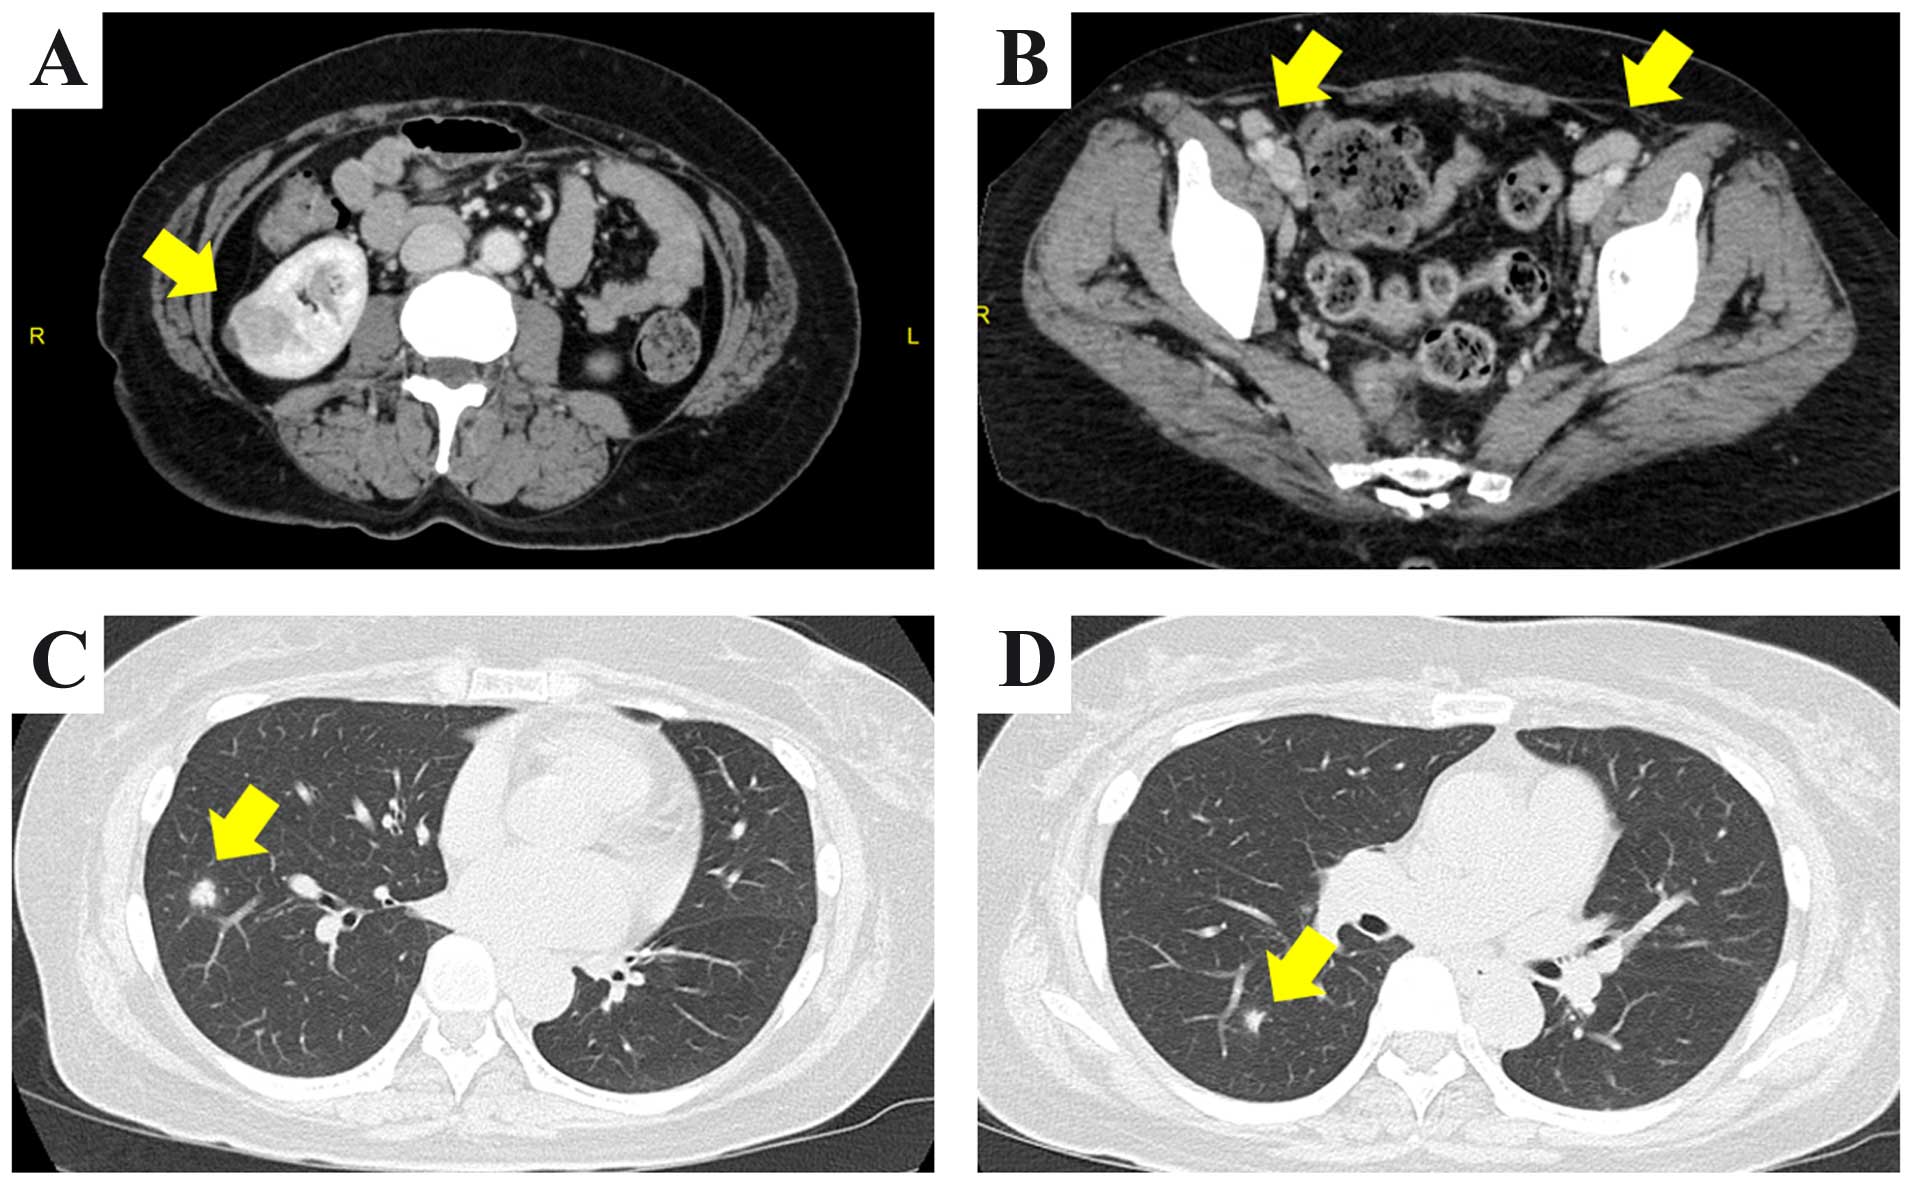

A 56-year old woman underwent medical examination by a physician. The patient was asymptomatic prior to hospitalization. Computed tomography (CT) was performed. Abdominal CT revealed a 22-mm mass with a cystic area in the right kidney and multiple enlarged lymph nodes in the common iliac, external iliac and groin areas bilaterally (Fig. 1A and B). The chest CT revealed multiple pulmonary nodules bilaterally, the largest measuring 15 mm (Fig. 1C and D). The laboratory tests revealed mild elevation of the C-reactive protein levels to 1.16 mg/dl (normal range, ≤0.14 mg/dl). The levels of tumor markers, such as squamous cell carcinoma antigen, carbohydrate antigen 19-9, carcinoembryonic antigen (CEA), cytokeratin 19 fragment and pro-gastrin-releasing peptide, were within the normal range. The serum concentration of soluble interleukin-2 receptor (sIL-2R) was increased to 914 U/ml (reference range, 122–496 U/ml). [18F] 2-fluoro-2-deoxy-d-glucose (18F-FDG) positron emission tomography showed high FDG uptake by multiple enlarged lymph nodes, whereas the right kidney mass and the pulmonary nodules exhibited no increased uptake. A right inguinal lymph node biopsy was first performed, since malignant lymphoma was suspected. On microscopic examination, there were sheets of lymphoid cells and numerous lymphoid follicles; however, there was no evidence of tumor cells (Fig. 2) and the lymph node enlargement was diagnosed as reactive lymphoid hyperplasia. Since the right renal tumor was suspected to be RCC, laparoscopic partial nephrectomy was performed, without any complications. The resected tumor was sized 25 mm and was well-circumscribed; histologically, it was composed of cells with eosinophilic cytoplasm arranged in glandular and cribriform patterns (Figs. 3 and 4). Immunohistochemically, almost all the tumor cells were diffusely positive for pancytokeratin (AE1/AE3), cytokeratin 7 and E-cadherin. Immunoreactivity for CD10, α-methylacyl-CoA racemase, 34βE12, c-kit, anaplastic lymphoma kinase, thyroid transcription factor-1, p63 and CEA was not detected in the tumor cells. These findings suggested that the tumor was a RCC with distal tubular characteristics. However, the findings were not typical. The case was referred for expert consultation, and the final pathological diagnosis was unclassified RCC. One month after surgery, a thoracic CT scan revealed spontaneous regression of the pulmonary nodules (Fig. 5). However, the enlargement of the lymph nodes did not subside. Surveillance CT scans at 3 months revealed no evidence of recurrence or progression of the pulmonary nodules and lymph nodes. In addition, the level of sIL-2R had decreased to 511 U/ml.

Figure 1.

(A-D) Computed tomography (CT) scan findings at diagnosis of this case. (A) Abdominal CT revealed a 22-mm enhanced mass with a cystic area in the right kidney (arrow), with (B) multiple enlarged lymph nodes in the common iliac, external iliac and groin areas, bilaterally (arrows). (C and D) Thoracic CT scan revealed several nodules with a maximum diameter of 15 mm in the lung (arrows).